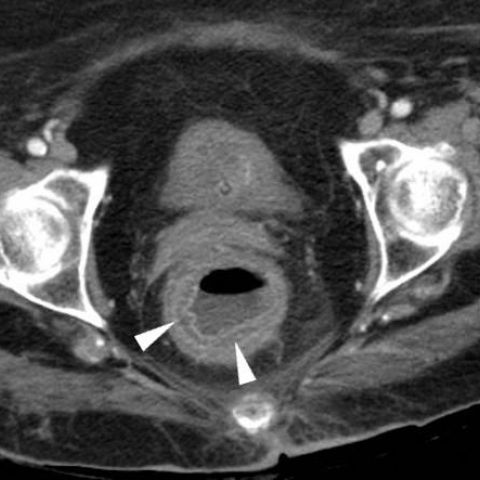

Proctitis refers to inflammation of the rectal mucosa. There are numerous causes of proctitis. These include infections, radiations, and immunosuppression. Exposure to few chemicals can cause proctitis. It may even involve colon, hence called 'chemical colitis'. Following are the chemicals associated with chemical proctitis and chemical colitis: - alcohol - formalin - acetic acid - sulfuric acid - glutaraldehyde - herbal enema - ergotamines - ammonia -disodium hydroxide - hydrogen peroxide - chloroxylenol - potassium permanganate Reference: https://www.eurorad.org/case/15787 Image via: https://www.google.com/url?sa=i&url=https%3A%2F%2Fwww.eurorad.org%2Fcase%2F15787&psig=AOvVaw0lk_Fr6p23YXPE2OUiDORG&ust=1644566906413000&source=images&cd=vfe&ved=0CAsQjRxqFwoTCKi3rpvX9PUCFQAAAAAdAAAAABAD